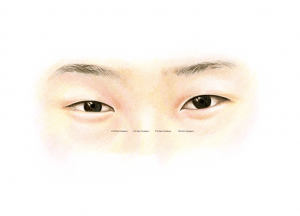

The basic, anatomical differences in Asian and Caucasian eyelids

Anatomically speaking, there are a number of subtle differences in the upper eyelids of East Asians compared to the eyelids of Europeans and Sub-Saharan Africans. While some East Asians have an eyelid crease and some do not, there is also a large variation in the skin fold position of the upper eyelid in East Asia. The position of the upper eyelid skin fold can vary from 1 mm above the lash line to approximately 10 mm, but when people come to the ELZA Institute for oculoplastic surgery, the changes they desire is very individual, but usually the goal is to obtain a more energetic, youthful and natural look.

The most commonly performed eyelid surgery in people from East Asia is sometimes referred to as “double eyelid surgery”, and is a cosmetic surgical method that reconstructs the skin of the upper eyelid. Often oculoplastic surgeons also partially remove any skin surplus, which is a natural consequence of ageing. We oculoplastic surgeons can also create an eyelid crease – something that is naturally missing in people from East Asia (which is sometimes referred to as a “mono-lid”).